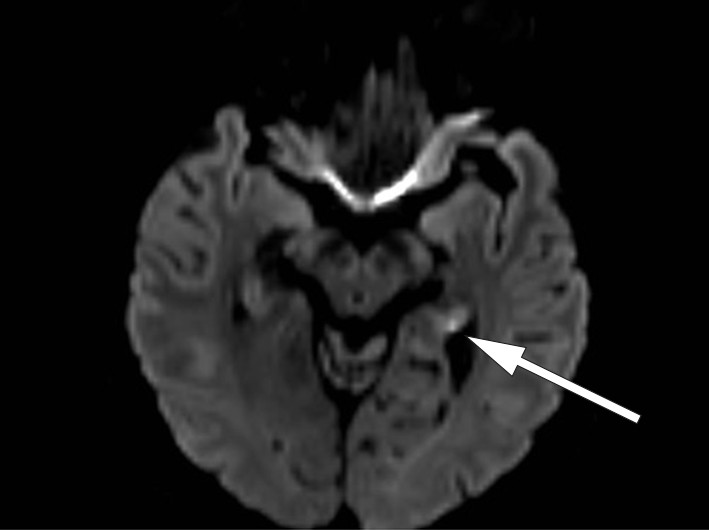

Vår pasient hadde normalt EEG og normale blodprøver. MR caput på 3 Tesla-maskin viste normale forhold på ordinær diffusjonsvektet snittserie med 4 mm tykke snitt. På diffusjonsvektet snittserie med 2 mm snitt ble det funnet to punktformede diffusjonsavvik på hver side av samme dato svarende til hippocampus (bilde 1 og 2).

MR-funnene er typiske for transitorisk global amnesi. Da slike lesjoner er såpass små, lar de seg best påvise ved 3 Tesla MR-maskin med en snittprotokoll som omfatter tynne (2 – 3 mm), tette (snittavstand 2 – 3 mm) diffusjonsvektede snitt, der snittserien anlegges parallelt med hippocampusstrukturenes lengdeakse. Lesjonene lar seg lettest avdekke 48 – 72 timer etter symptomstart. Lesjonene er ikke spesifikke for transitorisk global amnesi, og påvisning av slike MR-forandringer kan føre til en feilaktig hjerneinfarktdiagnose. Det kliniske bildet er avgjørende for å skille tilstanden fra isolerte hippocampusinfarkt (3, 4).

Vår pasient hadde et klinisk bilde vel forenlig med transitorisk global amnesi, med ledsagende typiske lesjoner på MR-bildet. MR-bilder seks uker etter symptomdebut viste komplett tilbakegang av aktuelle lesjoner.